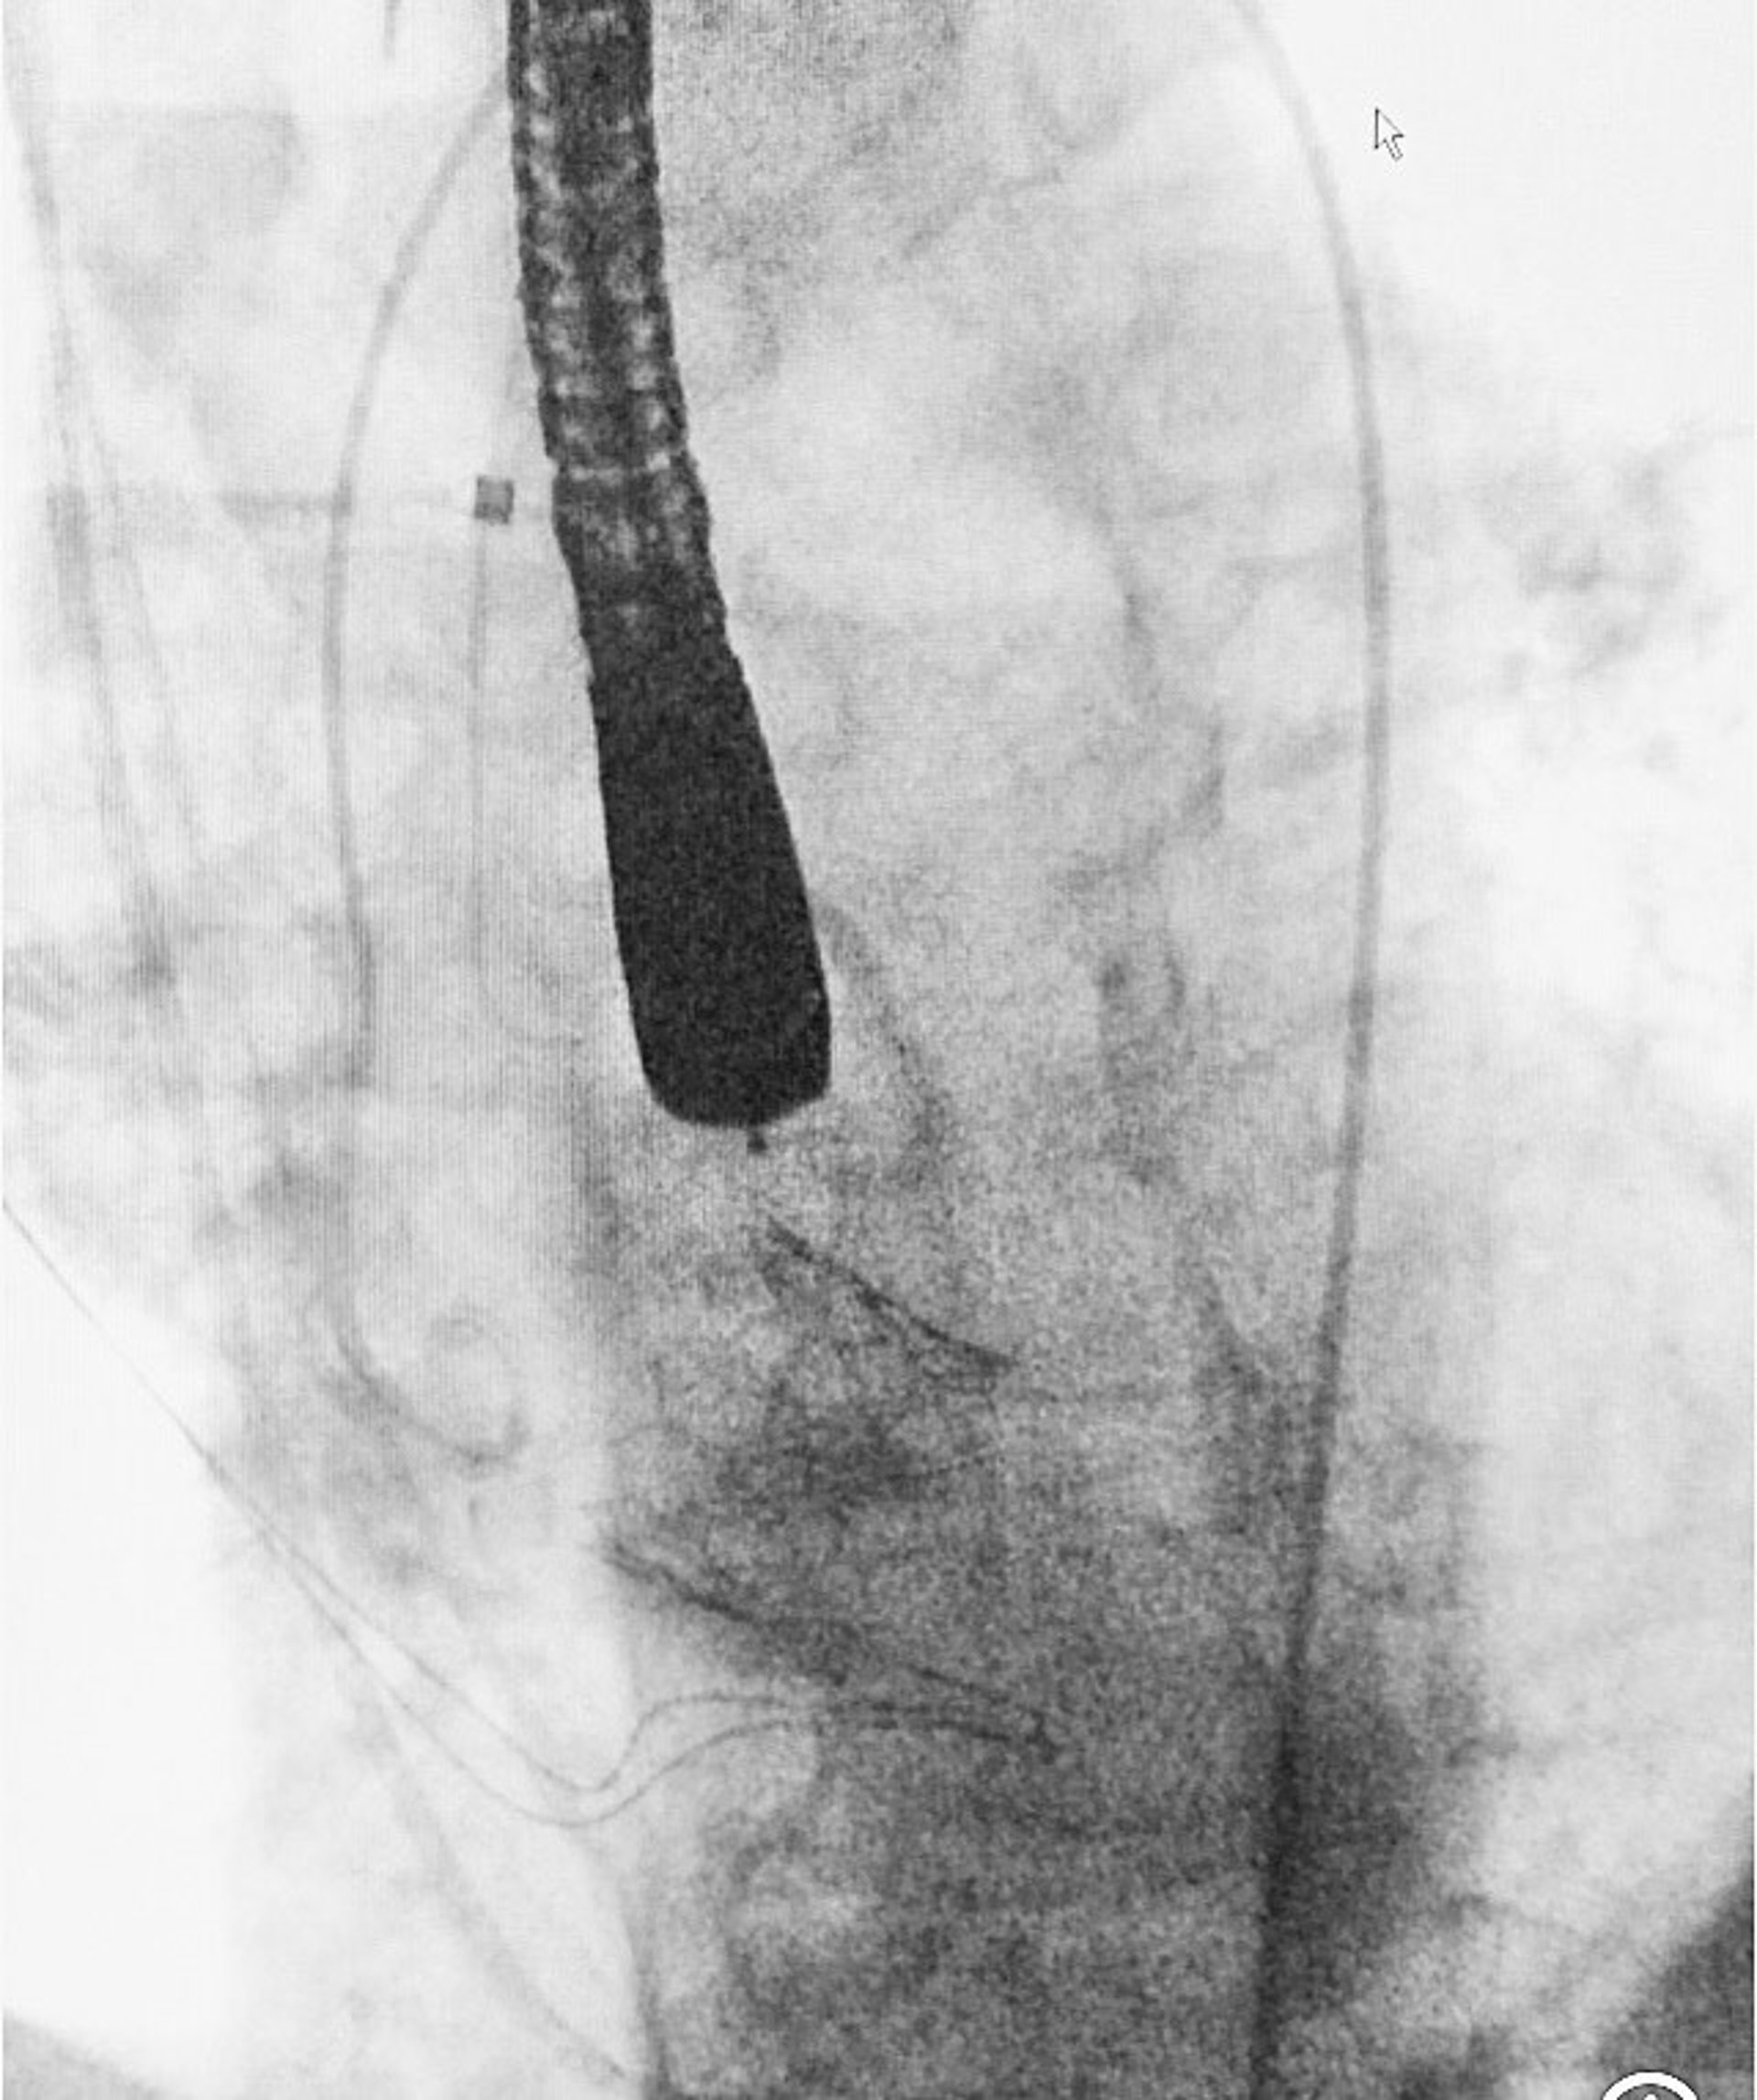

Nueva válvula aórtica percutánea por vía transaxilar, MYVAL, implantanda en el Hospital Universitario de Badajoz

El Servicio de Cirugía Cardiovascular del Complejo Hospitalario Universitario de Badajoz ha implantado una nueva válvula aórtica percutánea por vía transaxilar, la válvula MYVAL, que hasta ahora no se había implantado en España por ningún equipo de cirugía cardiovascular.

La vía de abordaje transaxilar se realiza mediante una pequeña incisión en la región subclavicular izquierda, donde se suelen hacer las incisiones para el implante de marcapasos y por ahí se accede mediante disección a la arteria axilar, sin tener que abrir el tórax.

Se realiza un punto de sutura en la arteria y con un sistema de punción se procede a la inserción de un introductor por el que van a navegar guías y catéteres hasta el corazón.

El procedimiento es manejado mediante fluoroscopia con rayos X y hace posible el implante de la válvula protésica sin parar el corazón ni someter al paciente a circulación extracorpórea, como sería necesario en una cirugía convencional.